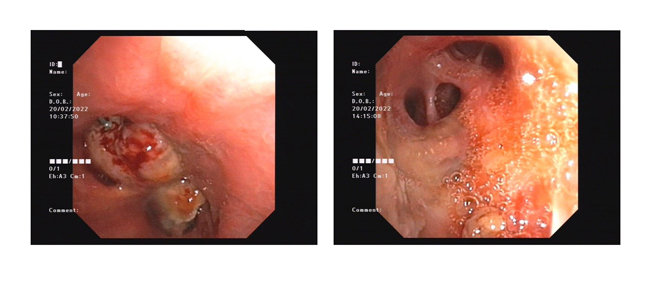

支氣管鏡下微波消融術(shù)前后對比

據(jù)黃德良主任介紹,劉健患者這次因肺鱗癌引起氣喘問題過來求治的。入院后經(jīng)過完善檢查診斷為右肺鱗癌并胸膜、肺門、縱膈淋巴結(jié)轉(zhuǎn)移,已是T4N2M1屬于肺癌IV期了?!爱?dāng)時情況非常緊迫,患者右主支氣管主干完全堵塞,左主支氣管堵塞,雖然之前在外院做了支架,但支架近端也有腫瘤導(dǎo)致大部分的堵塞。病人呼吸困難,經(jīng)皮血氧低于80%。在麻醉科,氣管鏡室和8樓醫(yī)護共同努力下給病人行右主支氣管腫物微波消融術(shù),術(shù)后氣道恢復(fù)通暢,右肺完全復(fù)張!患者手術(shù)中還出行反復(fù)出血,情況非常不理想,幸得患者家屬無條件的信任,經(jīng)過團隊的共同努力,歷時3個多小時的手術(shù)還是順利完成。目前病人已經(jīng)可以下床走路,經(jīng)皮血氧恢復(fù)至95%。”2月15日,經(jīng)過黃教授團隊的評估后,患者接受了介入化療方案,術(shù)后患者呼吸困難癥狀得到進一步改善,指尖血氧好轉(zhuǎn)。在2月20日再次接受氣管鏡下雙側(cè)主支氣管腫物微波消融術(shù)。3月1日復(fù)查了CT,患者腫塊縮小,右肺復(fù)張。